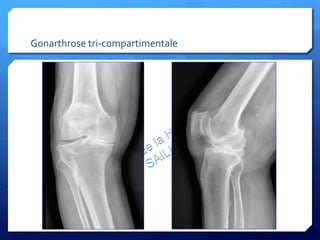

Gonarthrose

tri-­‐compartimentale

• 8.

• 9.